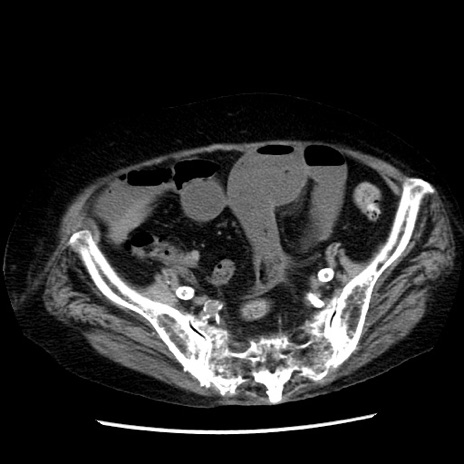

冠状断像

【症例】 90歳代女性

【主訴】 腹痛・嘔吐

【現病歴】今朝から左側腹部痛を認めた。 経過観察していたが、嘔吐を認めたため来院。

【既往歴】 子宮癌術後

【身体所見】 意識清明、BP 127/54mmHg、P 98bpm Sp02 95%(RA)、BT 35.8°C、腹部平坦・軟腸ぜん動音聴取良好、右下腹部圧痛(+) 反跳痛なし

【データ】WBC 9800、CRP 0.46